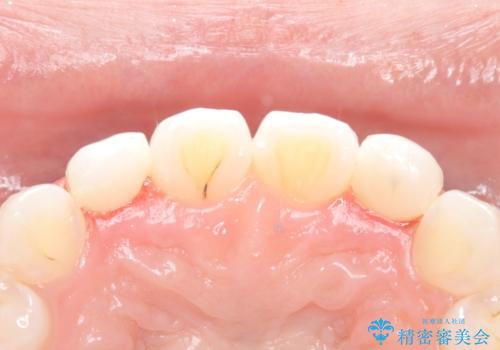

【ダイレクトボンディング】歯を削らずに綺麗にしたい。

- 矯正治療終了後、矮小歯の修復を希望された患者様です。

治療選択肢として、セラミッククラウン、ラミネートベニア、ダイレクトボンディングを提示したところなるべく歯を削りたくないとのことでダイレクトボンディングにて治療を行いました。

デメリットとして経年劣化が起こることによる変色リスク及びセラミックに比べ汚れがつきやすいことが挙げられます。